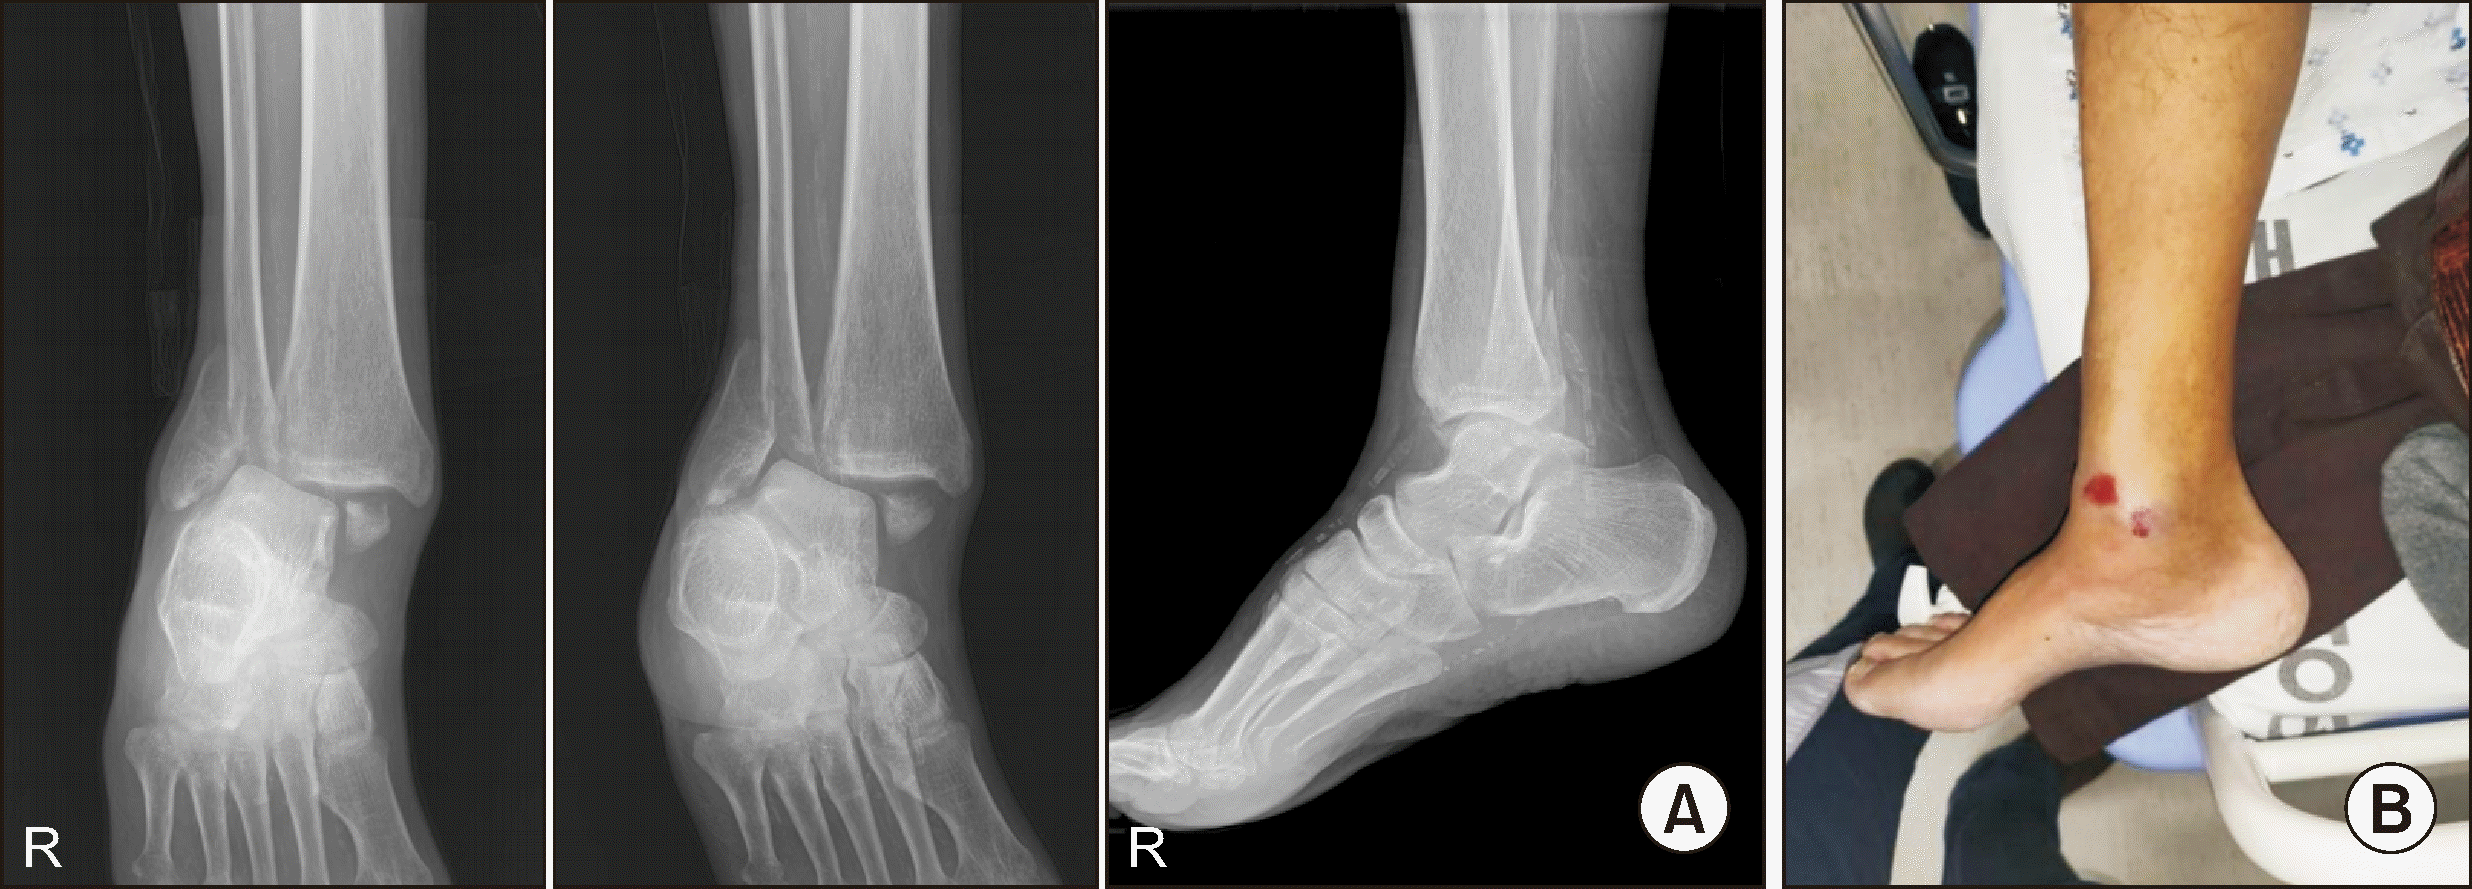

Follow-up visits were promising: 2 months after TTC fusion, the patient could walk short distances without difficulty (Fig. 15). The most recent follow-up, 2 years post-TTC fusion, showed no major complications. The patient was able to engage in light daily activities. Radiograph images confirmed well-maintained fusion, with the exception of a broken screw in the second from the distal portion (Fig. 16).

Figure 12

Findings at 8 months post-tibiotalocalcaneal fusion showing fever and operation site infection, accompanied by concurrent metal failure.